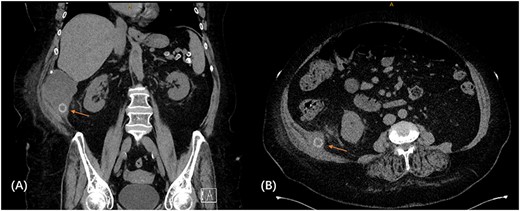

We proceeded with a multiphase computed tomography (CT) scan which was suggestive of a mixed density lesion measuring 62 × 86 × 98 mm arising from the right posterior transverse abdominis/internal oblique muscle, with a well-defined rounded calcific focus at its inferior aspect likely representing a dropped gallstone (GS) associated with abscess formation (Fig. 1). She was commenced on intravenous antibiotics and, in review of her medical comorbidities and DAPT on board, underwent image-guided percutaneous drainage of the gallstone associated abscess collection in the first instance. Following a course of intravenous and oral antibiotics, she was followed up in the outpatient clinic where the drain was removed after 9 days as the output was serous and minimal. Clearance from anaesthetics and cardiology were obtained during pre-operative evaluation of fitness towards surgery, including an ECHO which demonstrated severe left atrial enlargement and moderate mitral stenosis but normal systolic function. DAPT was withhold since initial admission. She underwent an elective procedure 4 weeks later from the initial presentation with pre-operative CT-guided drain localization of the gallstone (Fig. 2) followed by an extra-peritoneal approach of exploration of the right flank. A single 18 × 15 × 14 mm intramuscular gallstone was removed from a deep intramuscular abscess cavity at 6 cm, with fibrous and inflamed tissue surrounding the stone (Fig. 3). Histopathology demonstrated a gallstone with acute inflammation and acellular debris. The postoperative course was uncomplicated with patient discharged on Day 3 post operation and remained well at outpatient follow-up with DAPT restarted.

CT scan demonstrating retained gallstone with associated abscess ~62 × 86 × 98 mm in the right flank involving the right posterior transverse abdominis/internal oblique muscle in the coronal (A) and axial (B) views.